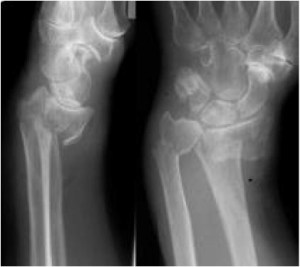

Wrist fractures